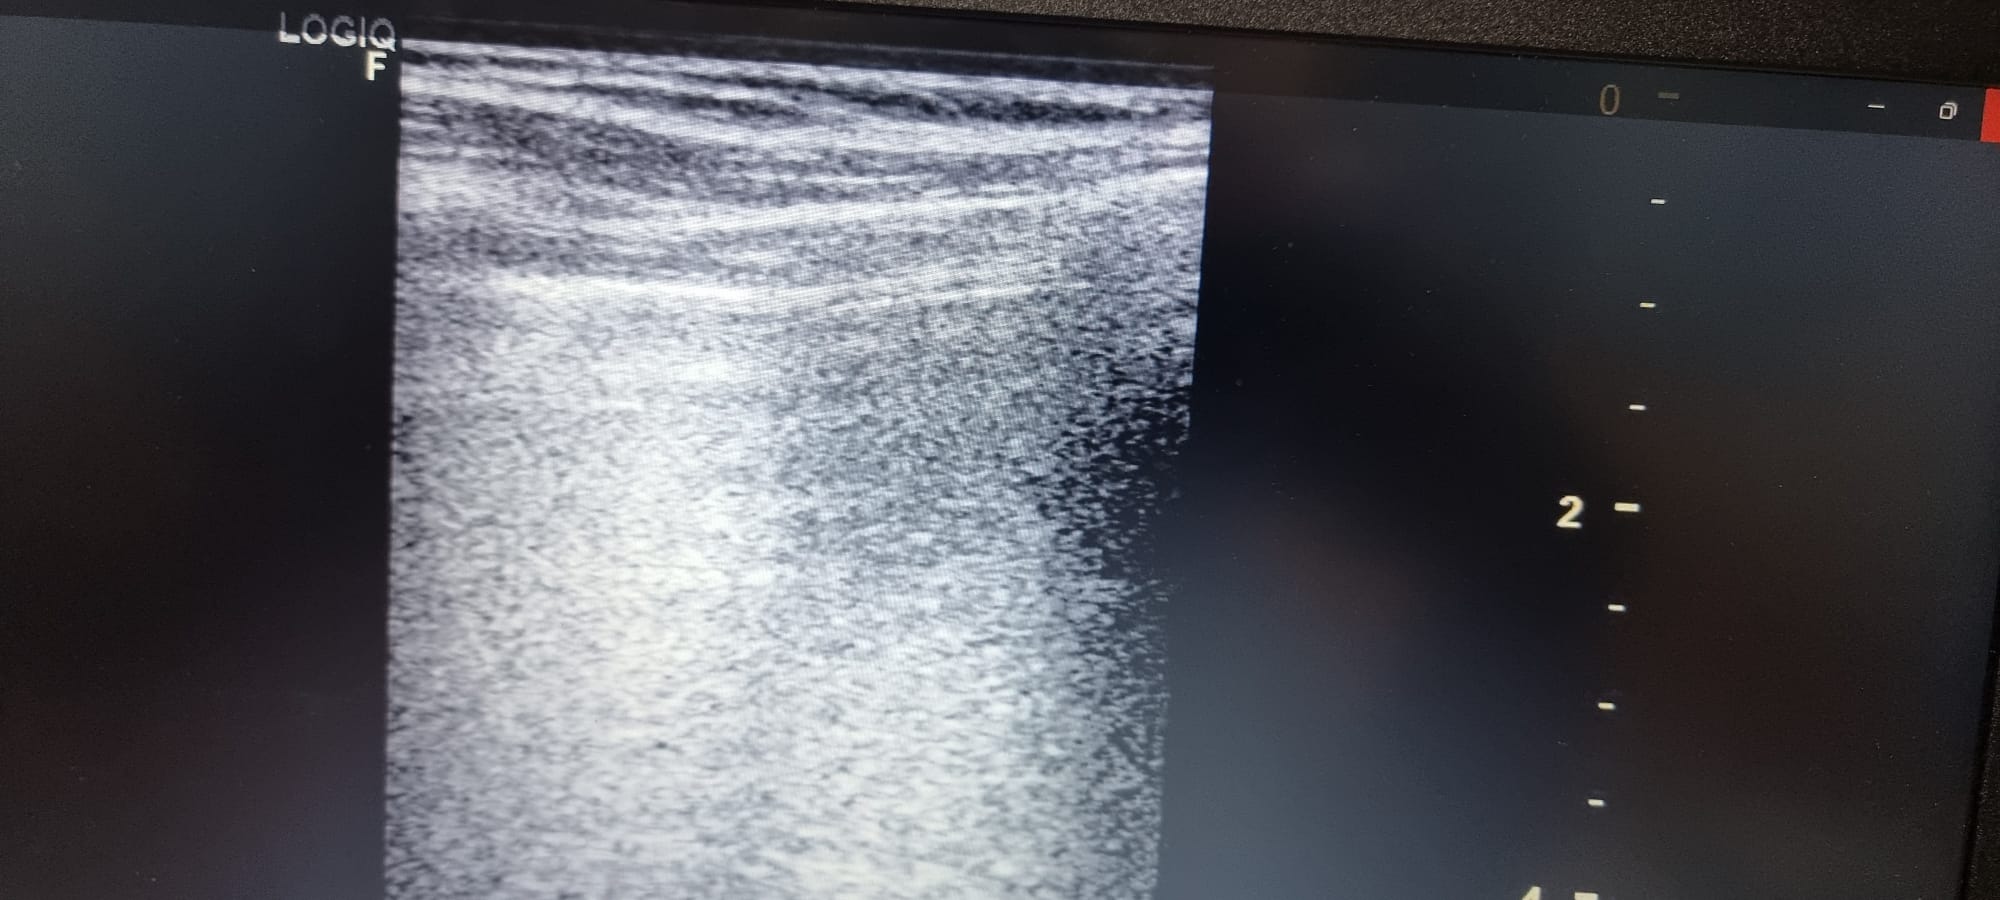

Se observa en base pulmonar izquierda defecto pleural triangullar (comparado con el contralateral).

La ecografía clínica pulmonar, nos aporta gran información que complementa la hipotesis dx, en este caso no acertada porque pensabamos mas en un TEP ya que nunca habiamos visto un derrame pleural en ecografía. Este era mínimo y no detectable con Rx Tx, con los conocimientos de la normalidad pudimos ver que había una imagen patologica comparando con el contralateral.